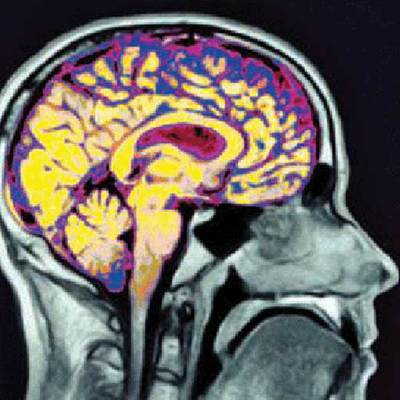

La ciencia que lee la mente

Los neurólogos detectan en el cerebro la 'firma' de la ideología y de la espiritualidad

Déjame ver tu cerebro... y te diré quién eres. Te diré, en concreto, a quién votas; si eres sincero o mentiroso; o si, como Enrique Iglesias, eres capaz de tener una experiencia religiosa. Y si además de ver tu cerebro me dejas tocarlo, podré inducirte desde un orgasmo a un viaje astral. Cantantes y metáforas aparte, los propios neurocientíficos advierten de que conviene tomarse en serio las posibles consecuencias derivadas del hecho de que empiezan a investigarse en el cerebro las bases biológicas, el hardware, de cuestiones tan íntimas y en apariencia intangibles como la ideología o la personalidad. No en vano la neuroética es un área en auge.

Los autores de un trabajo publicado recientemente en la revista Nature Neuroscience aseguraban haber hallado diferencias en el funcionamiento de un cerebro liberal frente a otro conservador. En pocas palabras: el primero reacciona mejor ante los cambios, mientras que el segundo es más rígido.

"Esta investigación demuestra que se empieza a dilucidar cómo un producto abstracto, aparentemente inefable de la mente, como la ideología, tiene su reflejo en el cerebro humano", dice Amodio. ¿Alguien se escandaliza por esta afirmación? ¿Alguien piensa que es absurdo que pueda verse algo así en un escáner cerebral? No los neurocientíficos, desde luego. Para ellos está clarísimo, y es perfectamente esperable, que cerebros que piensan distinto, que reaccionan distinto ante un mismo estímulo, funcionen de forma diferente; medir esa diferencia es sólo cosa de tener el instrumento adecuado.

"Todo, y todo es todo, está en el cerebro", dice Alberto Ferrús, director del Instituto Cajal de Neurociencias del CSIC, en Madrid. "La sensación de estar enamorado o enfadado, la religión... todo se traduce en moléculas, en algo físico que hay en el cerebro".

En los años noventa, cuando aparecieron las primeras técnicas para estudiar el cerebro humano en vivo y en directo -en acción-, se supo que la corteza cerebral de muchos ciegos muestra diferencias apreciables respecto a la corteza de personas que ven; que el cerebro de los taxistas tiene más sitio para información espacial; o cómo actúa el cerebro de los ajedrecistas al jugar. ¿Qué hay de raro en dar un paso más y buscar la marca de la mentira o la espiritualidad? Nada de nada, dice Ferrús.